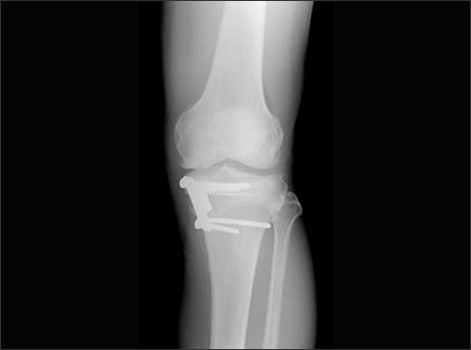

콘드로이친 효능 6.연골의 재생

콘드로이친은 연골 손상을 막을 뿐만 아니라 손상된 연골 주성분인 연골세포를 재생시킴으로써 연골 기능을 향상시키는데 도움을 주어 연골의 통증으로 고통 받는 분들에게는 보행 편의성을 증대시켜 삶의 질을 향상 시킬 수 있습니다.